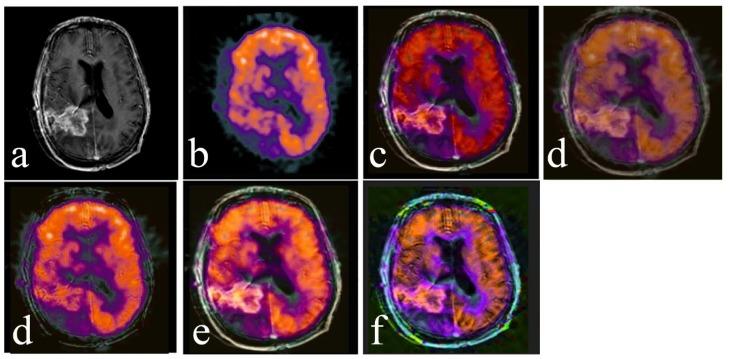

For the fusion of MRI gray scale images and PET color images, we used lesion region extracting based on the digital Curvelet transform (DCT) method. As curvelet transform has a better performance in detecting the edges, regions in each image are perfectly segmented. Curvelet decomposes each image into several low- and high-frequency sub-bands. Then, the entropy of each sub-band is calculated. By comparing the entropies and coefficients of the extracted regions, the best coefficients for the fused image are chosen. The fused image is obtained via inverse Curvelet transform. In order to assess the performance, the proposed method was compared with different fusion algorithms, both visually and statistically.

The analysis of the results showed that our proposed algorithm has high spectral and spatial resolution. According to the results of the quantitative fusion metrics, this method achieves an entropy value of 6.23, an MI of 1.88, and an SSIM of 0.6779. Comparison of these experiments with experiments of four other common fusion algorithms showed that our method is effective.

对于MRI灰度图像与PET彩色图像的融合,我们采用基于数字曲波变换(DCT)方法的病变区域提取。由于曲波变换在检测边缘方面具有更好的性能,每个图像中的区域都能被完美分割。曲波将每个图像分解为几个低频和高频子带。然后,计算每个子带的熵。通过比较提取区域的熵和系数,选择融合图像的最佳系数。通过逆曲波变换获得融合图像。为了评估性能,将所提出的方法与不同的融合算法在视觉和统计方面进行比较。

结果分析表明,我们提出的算法具有高光谱和空间分辨率。根据定量融合指标的结果,该方法的熵值为6.23,互信息(MI)为1.88,结构相似性指数测量值(SSIM)为0.6779。将这些实验与其他四种常见融合算法的实验进行比较表明,我们的方法是有效的。